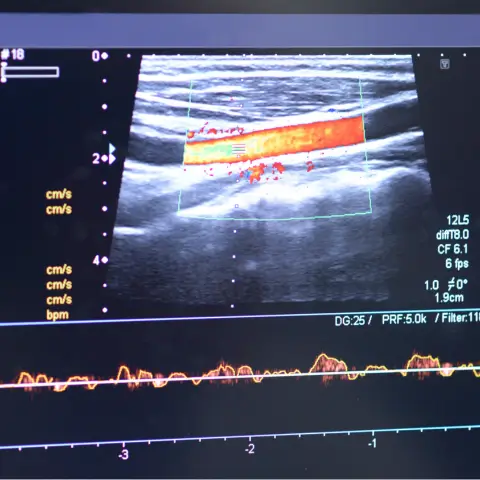

Vascular Ultrasound Detects Blockage

Vascular ultrasound is essential for diagnosing Varicose Veins, assessing blood flow and detecting faulty valves that lead to vein enlargement and discomfort. For Peripheral Arterial Disease, ultrasound identifies narrowing or blockages in leg arteries, guiding effective treatment planning.

In Deep Vein Thrombosis, ultrasound locates clots in deep veins and assesses risks like pulmonary embolism. For Carotid Artery Disease, it detects plaque buildup and narrowing in carotid arteries, key in stroke prevention. Ultrasound also measures Aortic Aneurysms in the abdominal aorta, helping prevent rupture.